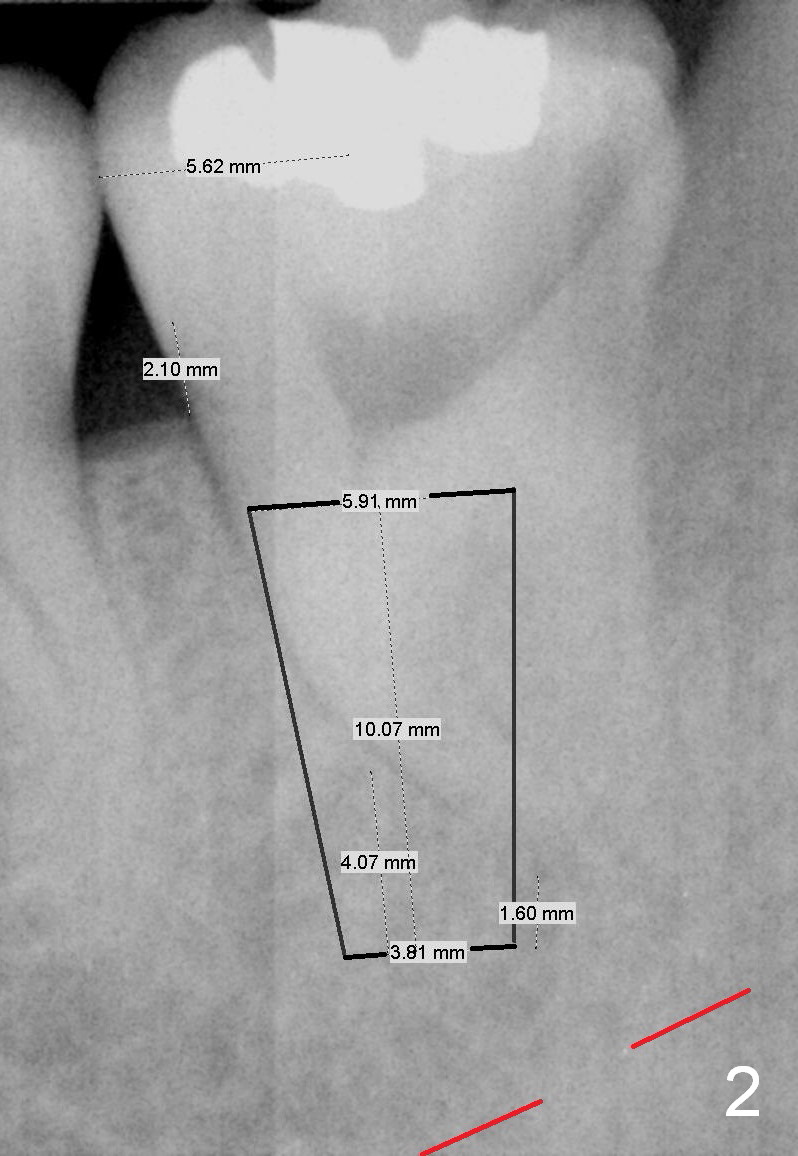

A 34-year-old man has distal deep caries of the lower 2nd molars. Root canal therapy turns out to be difficult on the right side due to bleach leakage. It would be also difficult to restore the distal defect. Finally he agrees to have extraction and implant. The result is good. He is ready to accept the same treatment for the left 2nd molar (Fig.1 (arrowheads: caries)). Metronidazole will be used for socket decontamination. Place a 5.9x10 mm bone-level implant 2 mm below the mesial crest (hopefully at the same level of the buccal crest) so that there is enough height to place an abutment (Fig.2). The apex of the implant is placed mesial to that of the root, since there is more bone, away from the superior border of the Inferior Alveolar Canal (red dashed line). The osteotomy is to be initiated in the middle of the mesial slope obliquely, more mesial (Fig.3 red line) than the center of the implant (green arrow). Once the lamina dura is penetrated, change the trajectory along the future long axis of the implant (Fig.4 red line). The depth will be 14 mm from the mesial gingival line (Fig.2). As the diameter of drills increases, the osteotomy tends to shift distal (Fig.5 pink arrow).